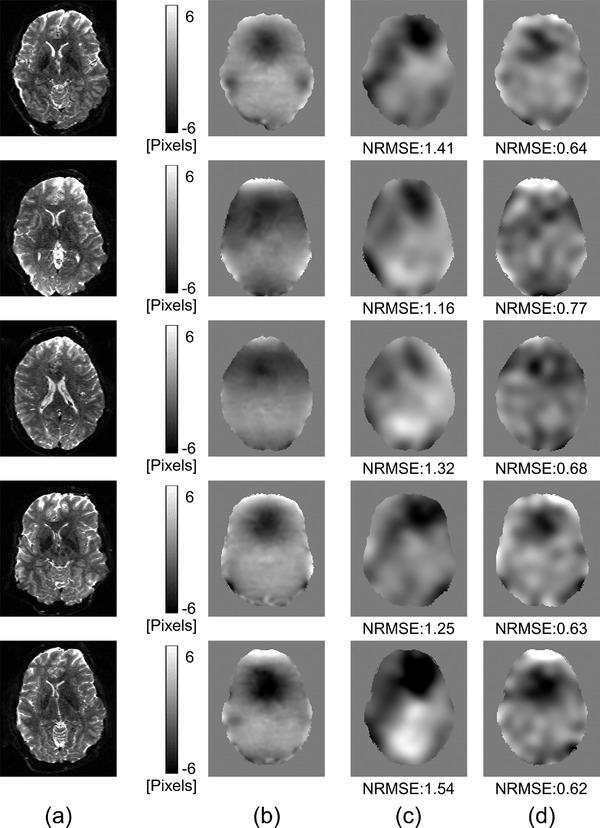

RESULTS

Using the simulated data, the means and standard deviations of the NRMSE values in the nonrigid registration-based method and proposed method were 1.29 ± 0.63 and 0.64 ± 0.30, respectively. The MI values in the proposed method were larger than those in the nonrigid registration-based method in all evaluated slices. For the real data, the proposed method improved the distortion, and the MI values in the proposed method were larger than those in the nonrigid registration-based method. In the estimation of the magnetic field inhomogeneity map, the NRMSE values in our method were smaller than those in the nonrigid registration-based method.

结果

使用模拟数据,基于非刚性配准的方法和所提出方法的 NRMSE 值的平均值和标准差分别为 1.29±0.63 和 0.64±0.30。在所有评估的切片中,所提出方法的 MI 值均大于基于非刚性配准的方法。对于真实数据,所提出的方法改善了失真,并且所提出的方法的 MI 值大于基于非刚性配准的方法。在磁场不均匀图的估计中,我们的方法的 NRMSE 值小于基于非刚性配准的方法。